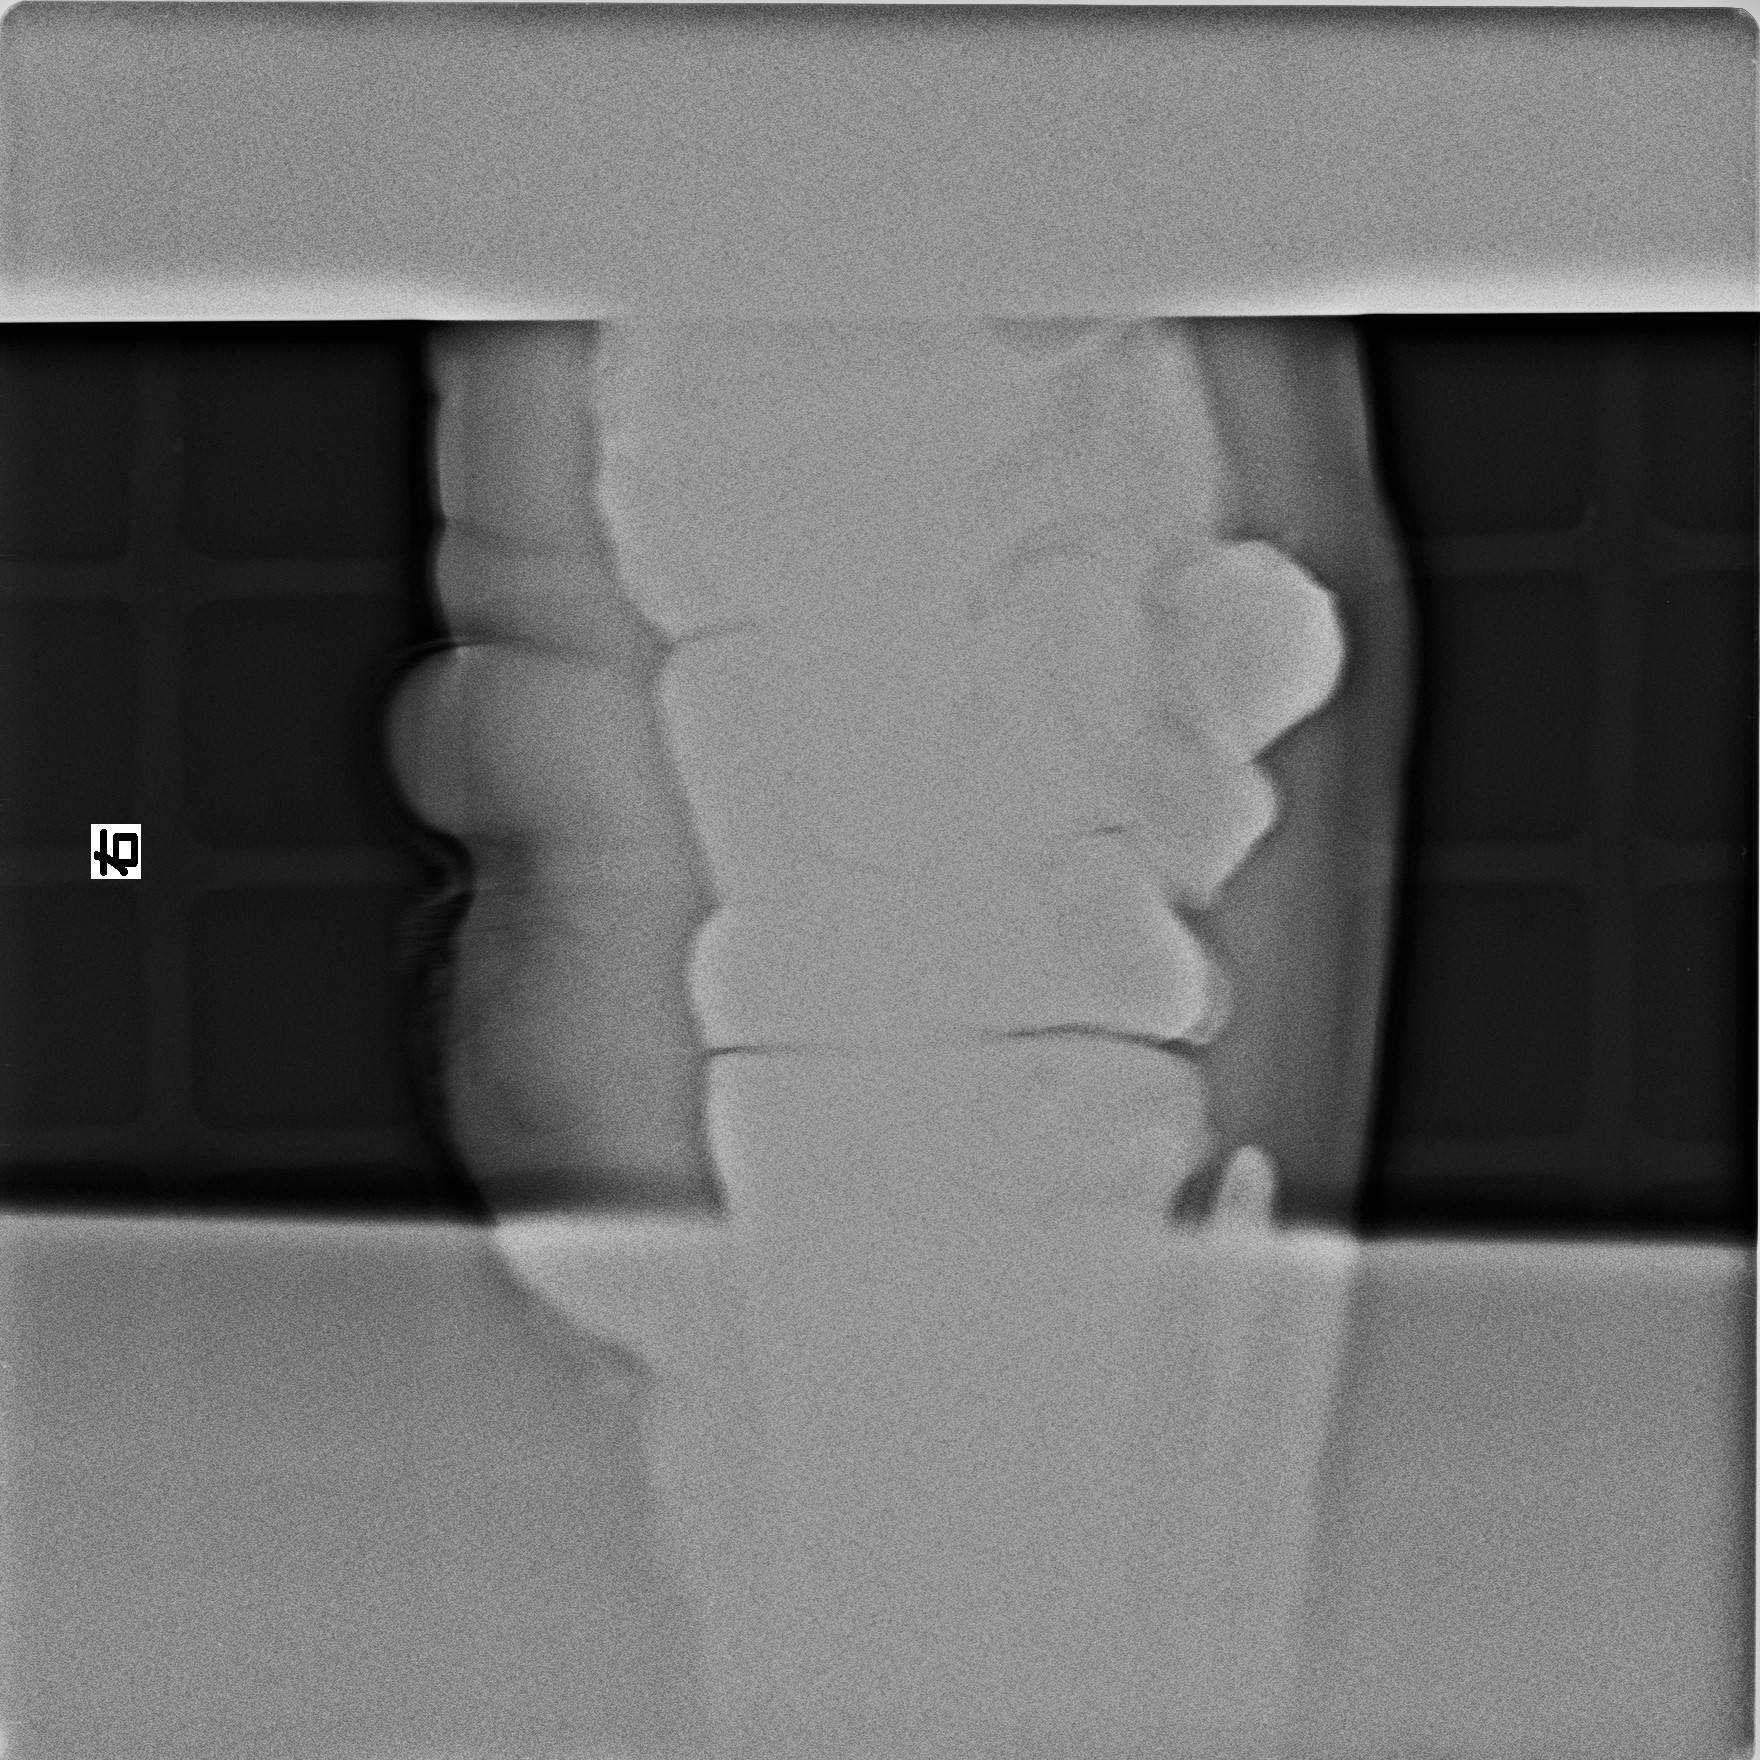

先月、現在は特に異常は見られませんが、健康時の脚の状態を撮影しました。

これは「そら」の右前腕を側面から撮影したものです。

平穏な時は準備の時と思い、緊急時に早急な対処ができるようにすることが目標です。